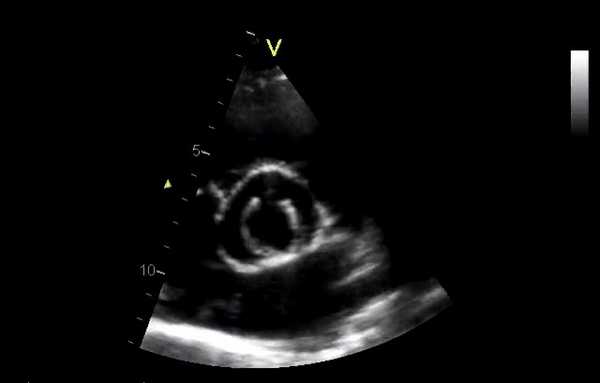

M-режим может давать некоторые характерные черты:

- Клапан Старра - Эдвардса обычно показывает две плотные, почти параллельные эхо-линии, представляющие пришивное кольцо и клетку. Видны только отражения эха от передней поверхности шара, которые отображаются в виде плотных линий. В открытом положении отражение от шара перемещается до линии клетки и никогда не выходит за ее пределы. В закрытом положении эхо-линия от клетки регистрируется на полпути между клеткой и пришивным кольцом в почти параллельном положении. Под кривыми клапана видны реверберации, представляющие отражения эха от задней поверхности шара.

- Клапан St Jude в открытом положении показывает параллельные линии диска, параллельные пришивному кольцу. В закрытом положении эхо-линии не записываются (диск находится внутри пришивного кольца).

- В биопротезах пришивное кольцо выглядит как непрерывная эхо-линия. Створки показывают эхо-кривые, похожие на нативные клапаны, с экскурсией створки, дающей коробчатую форму. Видны эхо-линии, представляющие 2 из 3 стентов.